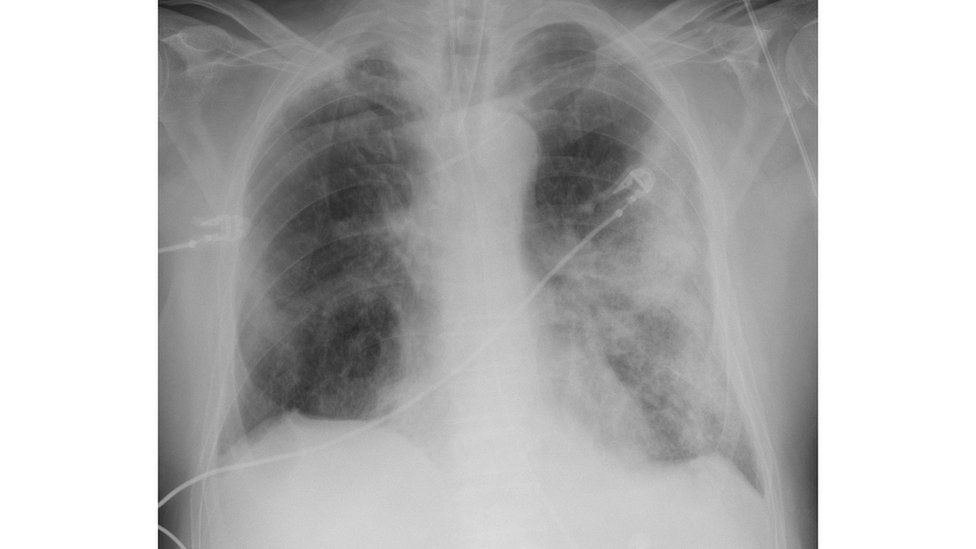

Raio X Do Torax Detecta Covid

Using Lung X Rays To Diagnose Covid 19 Imaging Technology News

Coronavirus X Rays Show Terrifying Damage In Lungs Of Covid 19 Victims World News Mirror Online

www.mirror.co.uk